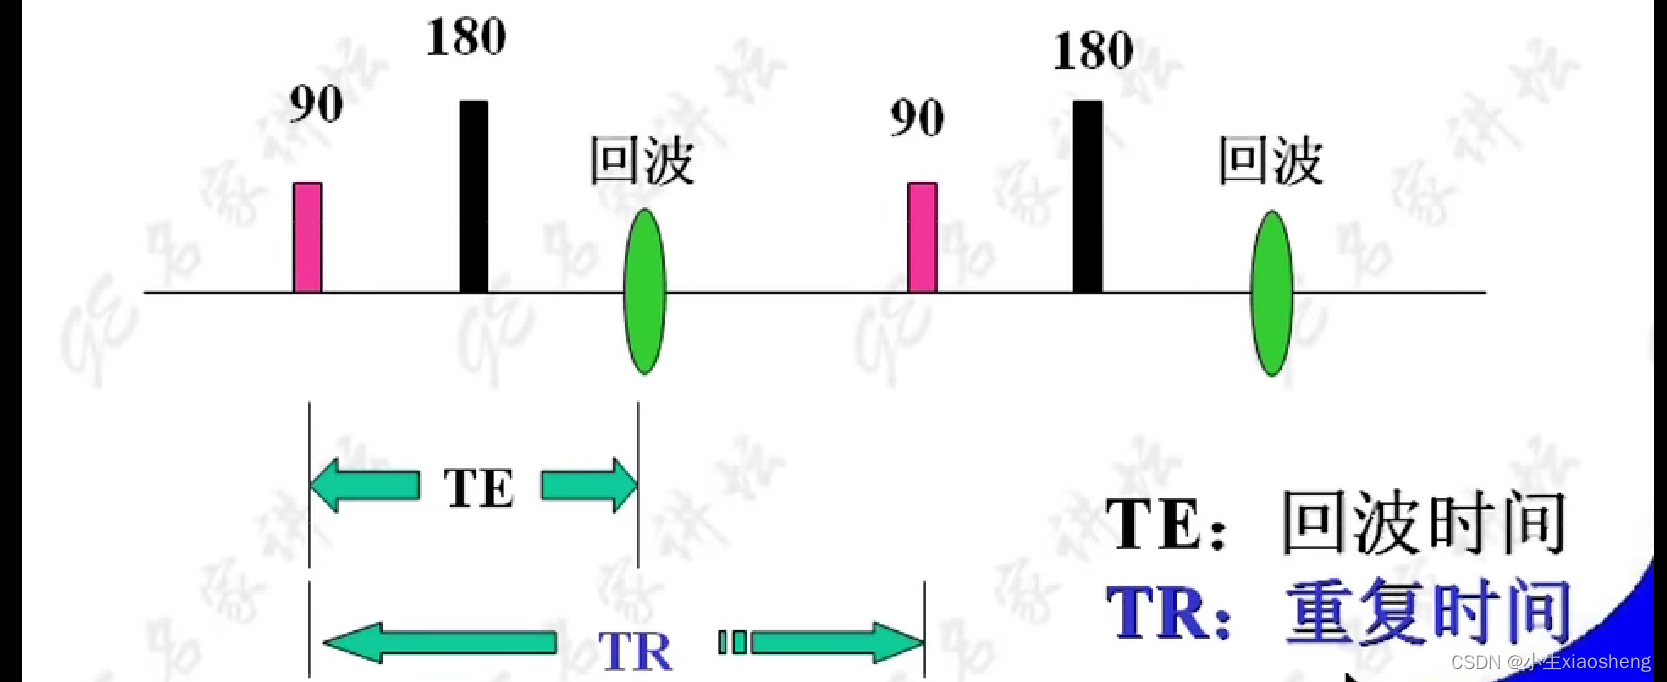

TR代表重复时间(repetition time),是指脉冲序列执行所需的时间

TE代表回波时间(echo time),是指产生宏观横向磁化矢量的脉冲中点到回波中点的时间间隔